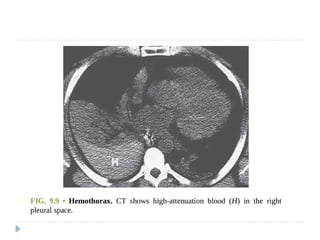

 Hemothorax:

 Bleeding into the pleural space

 may be secondary to trauma, aortic rupture, or pleural malignancy.

 Occasionally, it is seen in thromboembolic disease when

complicated by pulmonary infarction.